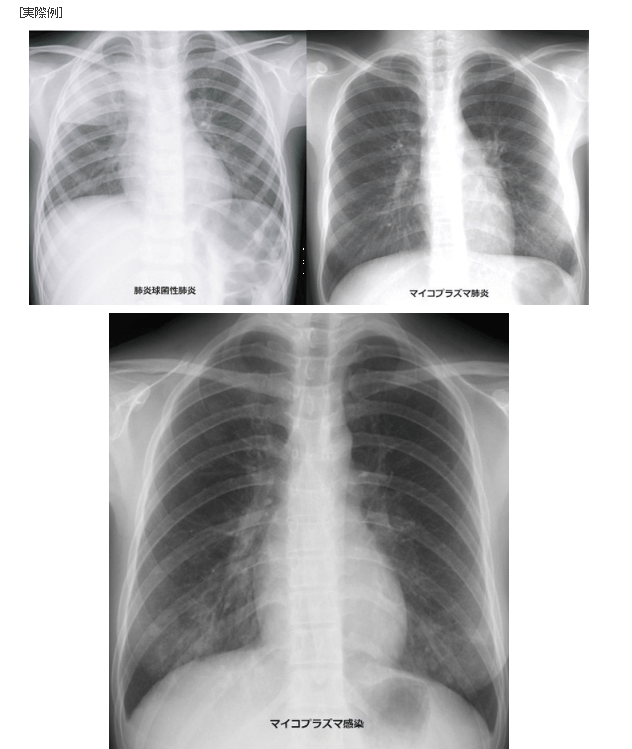

新型コロナ、死亡するのは「肺浸潤」というものが原因だった…。

新型コロナの特徴とは?かぜやインフルエンザと肺炎の違い